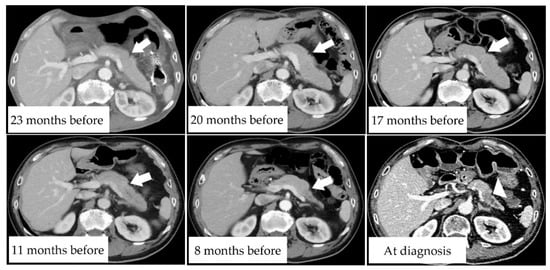

3.5. Case Presentation